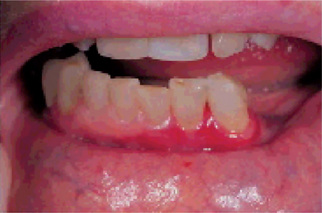

Oral mucous membrane lesions may be extremely severe and so painful that mastication is impossible. Mucosal vesicles or bullae occur which rupture and leave surfaces covered with a thick white or yellow exudate. Erosions of the pharynx are also common. The lips may exhibit ulceration with bloody crusting and are painful (Fig. 19-13A). The oral lesions may be the chief complaint of the patient, and understandably, have been mistaken for acute necrotizing ulcerative gingivostomatitis. Interestingly, however, it has been reported that the organisms of Vincent's infection are scarce in patients with this disease. The mucosal involvement in SJS is more severe and extensive than in EM major.

Figure 19-13 Stevens-Johnson syndrome.

Crusting ulcerated lesions of the oral cavity and lips (A), conjunctivitis (B), urethritis (C) are characteristics of the disease.